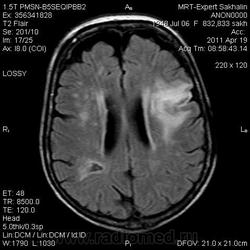

склоняюсь к кровизлиянию в левой теменной долей, начало перехода острой стадии в раннюю подострую( по периферии определяется повышение МРС по Т1 ВИ -метгемоглобин). Справа -старые кортикальные постишемческие глиозно-атрофические изменения. Контрастируется , вероятно за счет формирования участков ангионеогенза.

Это демиелинизирующий процесс, острая стадия, причем с геморрагическим пропитыванием в центре пораженных участков. В принципе, соответствует тяжелому рассеяному склерозу, хотя может быть и геморрагическая форма ОДЭМ. Также могут быть мозговые проявления системного васкулита: надо знать анамнез.

На фоне ДЭП изменений МР-картина ОНМК по ишемическому типу в бассейне ЛСМА с участками геморрагического пропитывания. Аналогичный участок но в более поздней фазе в задних конвнкситальных отделах правой теменной доли.

О.С., я согласен, что контрастирование нехарактерно для ОНМК, ведь в подострую стадию инфаркта наблюдается, как правило, гиральный тип усиления. Плюс, на ОНМК непохоже то, что поражено почти только белое вещество, а кора интактна. И потом, при такой локализации инфаркта обязательно должна быть яркая клиника, и уж никак не только "головная боль".

А средний мозг ?Там тоже очаги гиперинтенсивного по Т2сигнала.

Что касается снимочков мне кажется что зона патологического сигнала в левой гемисфере можно расценить как подострую стадию ОНМК с геморрагическим пропитыванием, справа как последствия ОНМК. При чем множественные очаги скорей всего как проявление ХМНК. И обязательно рекомендовать контрольное МРТ в динамике . Если это действительно ОНМК на фоне лечения отек уйдет и будет формированиться зона кистозно-глиозных изменений, а если отек будет нарастать значит надо думать о объемном процессе.